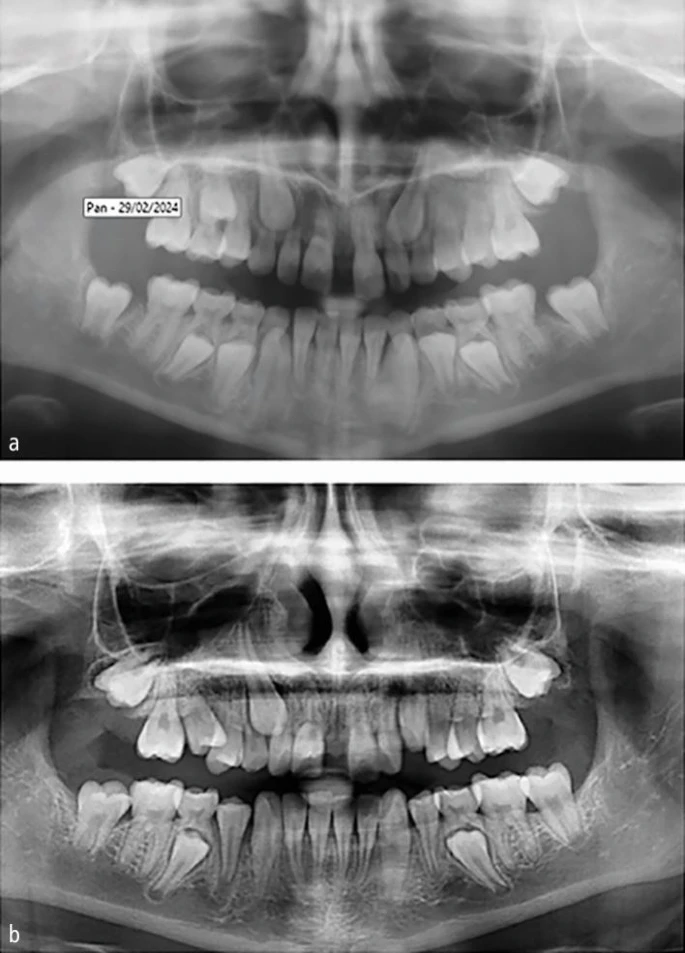

Для большинства врачей-стоматологов общей практики (ВСОП) такие методы, как прицельная рентгенография, окклюзионная рентгенография верхней челюсти или ортопантомограмма, являются легкодоступными в условиях клиники. Эти снимки могут предоставить essentialную информацию о развитии зубного ряда, в частности о постоянном верхнем клыке. Были предложены три критерия для оценки положения этого зуба на панорамном снимке (Рис. 1):

- Горизонтальное положение коронки клыка относительно вертикальной линии, проведенной между центральными резцами верхней челюсти (срединно-сагиттальная плоскость/срединная линия), основанное на пяти вертикальных секторах;

- Угол наклона длинной оси клыка относительно вертикальной линии, проведенной между центральными резцами верхней челюсти (срединно-сагиттальная плоскость);

- Высота расположения режущего бугра клыка относительно окклюзионной плоскости.

Ключевым прогностическим фактором успешного исхода, по-видимому, является рентгенологическое горизонтальное положение коронки клыка по отношению к срединно-сагиттальной плоскости (см. Рис. 1). На основе расстояния до средней линии (будь то классификация по секторам или измерение в мм) клиницисты могут оценить, прорежется ли верхний клык нормально или потребует дальнейшего вмешательства (Таблица 2).